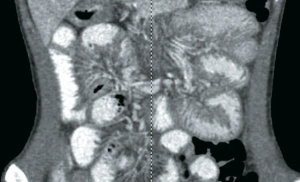

A 16-year-old male with a history of nephrotic syndrome and gastritis presents to the emergency department (ED) with worsening emesis, diarrhea, and abdominal pain of 3-weeks’ duration.